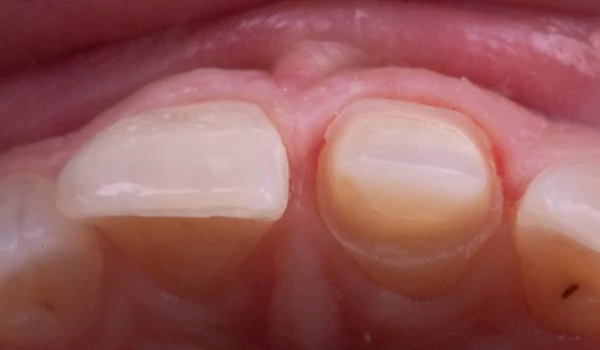

BevezetésA frontfogak traumás törései egyaránt megkövetelik az esztétikum és funkció tökéletes egyensúlyát – mindezt gyakran a páciens érzelmi nyomása alatt. Dr. Koray Kendir esetbemutatója azt szemlélteti, hogyan lehet egy korábban nem megfelelően kezelt centrális metszőt biomimetikus (a természetre emlékeztető) megközelítéssel és Kuraray Noritake termékek segítségével sikeresen rehabilitálni kuraraynoritake.eu. Az eset összefoglalásaEgy 23 éves nőbeteg jelentkezett egy hónappal a trauma után. A sérült 11-es fogon (FDI jelölés) korábban más szakorvos által végzett gyökérkezelést és direkt kompozit felépítést találtak, amely azonban esztétikailag és marginálisan is elégtelennek bizonyult (1. ábra) kuraraynoritake.eu. |

1. ábra. Klinikai helyzet kiinduló pont |